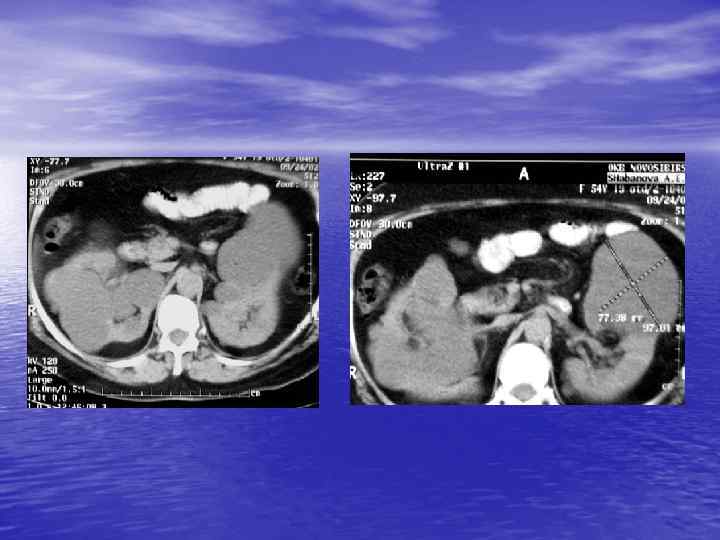

Структурный анализ Оценка основных макроскопических признаков: - положение - форма - размеры - характер контуров и структур патологически измененных участков

Структурный анализ

Денситометрический анализ Определение основных видов патологических образований: - обызвествленных - мягкотканных - жидкостных - жиросодержащих - воздухсодержащих

Денситометрия